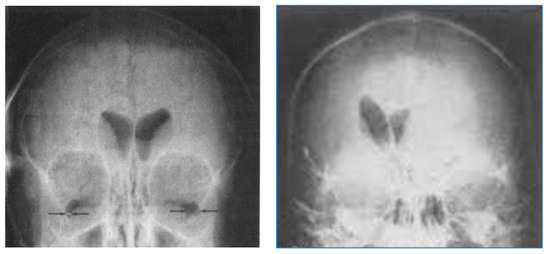

Figure 3.

Air studies, frontal views. Normal control (left) and patient with brain tumor in the left cerebral hemisphere (right). The CSF in the ventricular has been replaced by air. The air has a low signal (black appearance) and this creates contrast between the ventricular system and surrounding brain. In the normal air study on the left, the lateral ventricles are symmetrical. In the patient on the right both lateral ventricles are displaced to the right by a tumor in the left hemisphere (black arrow). There is encroachment of the brain into the left lateral ventricle and probable enlargement of the right lateral ventricle.